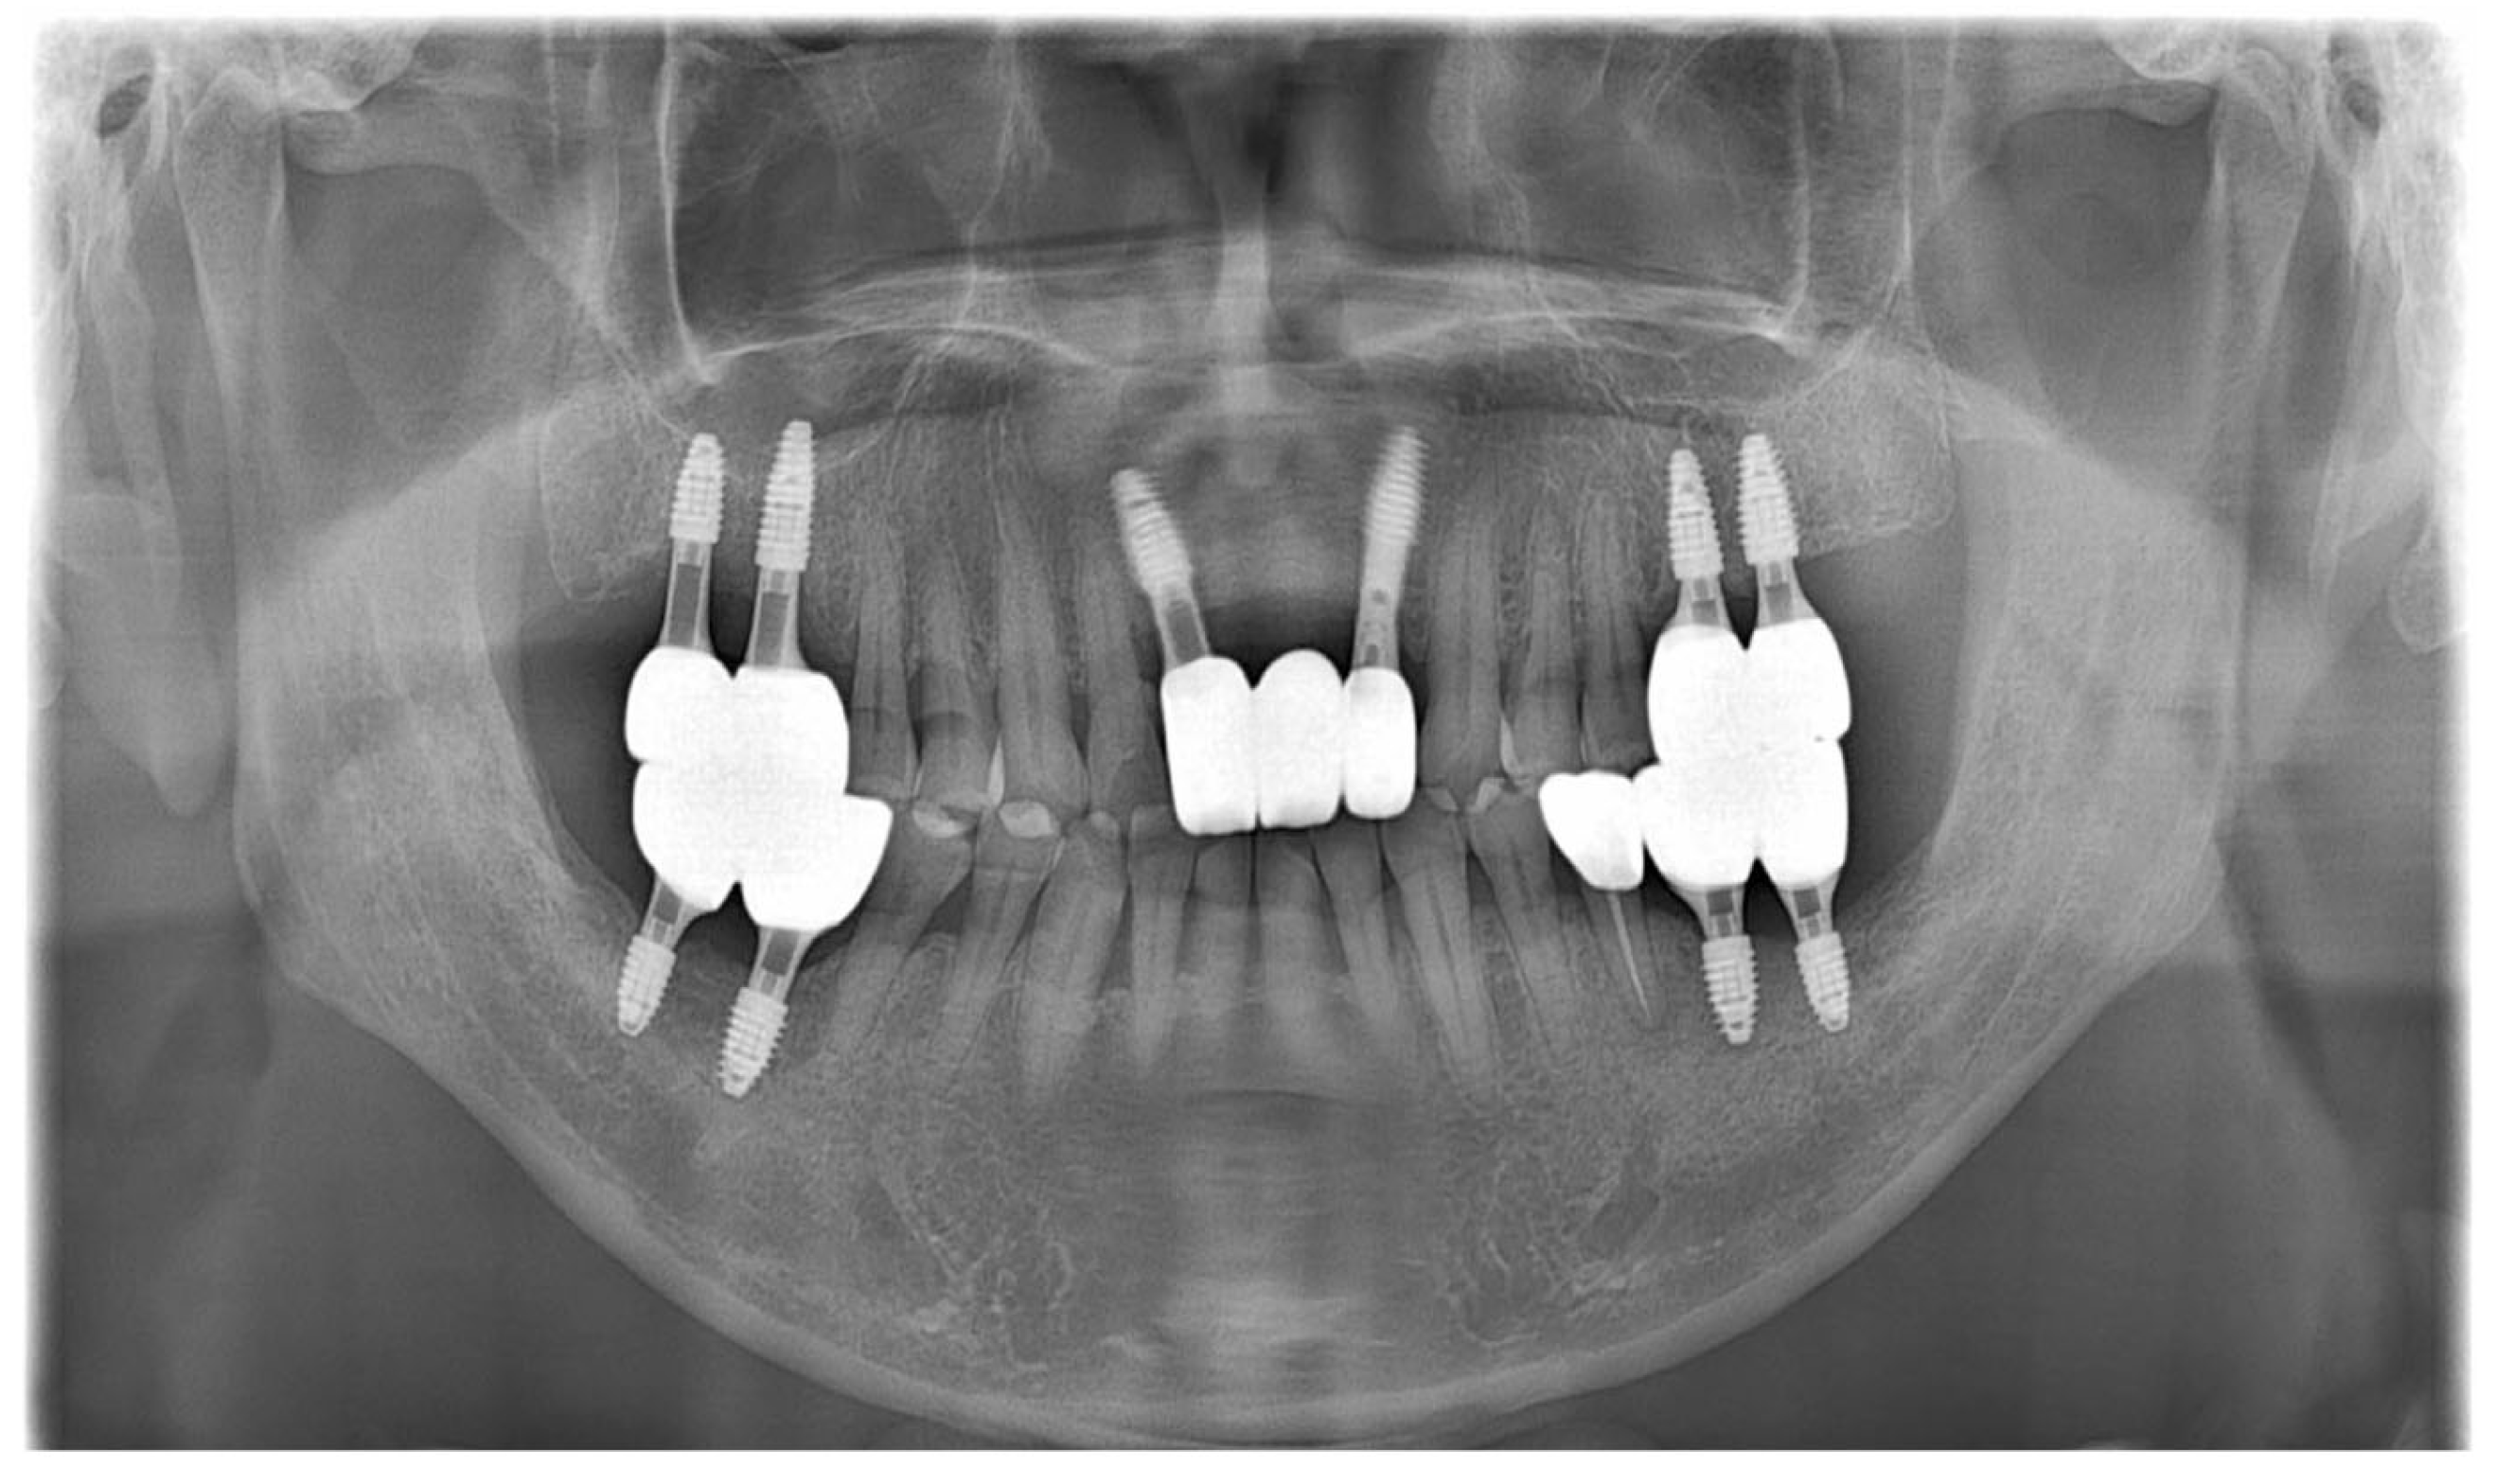

As part of the patient’s ongoing maintenance therapy, follow-up examinations were conducted every six months with routine dental plaque control. When required, additional periodontal treatment was provided during subsequent visits. Annual panoramic radiographs were taken to monitor the long-term prognosis of the implant. At the two-year follow-up, the implant prosthesis remained well maintained and functionally stable within the oral cavity (Figure 11).

Figure 11.

Panoramic radiograph after 2 years.